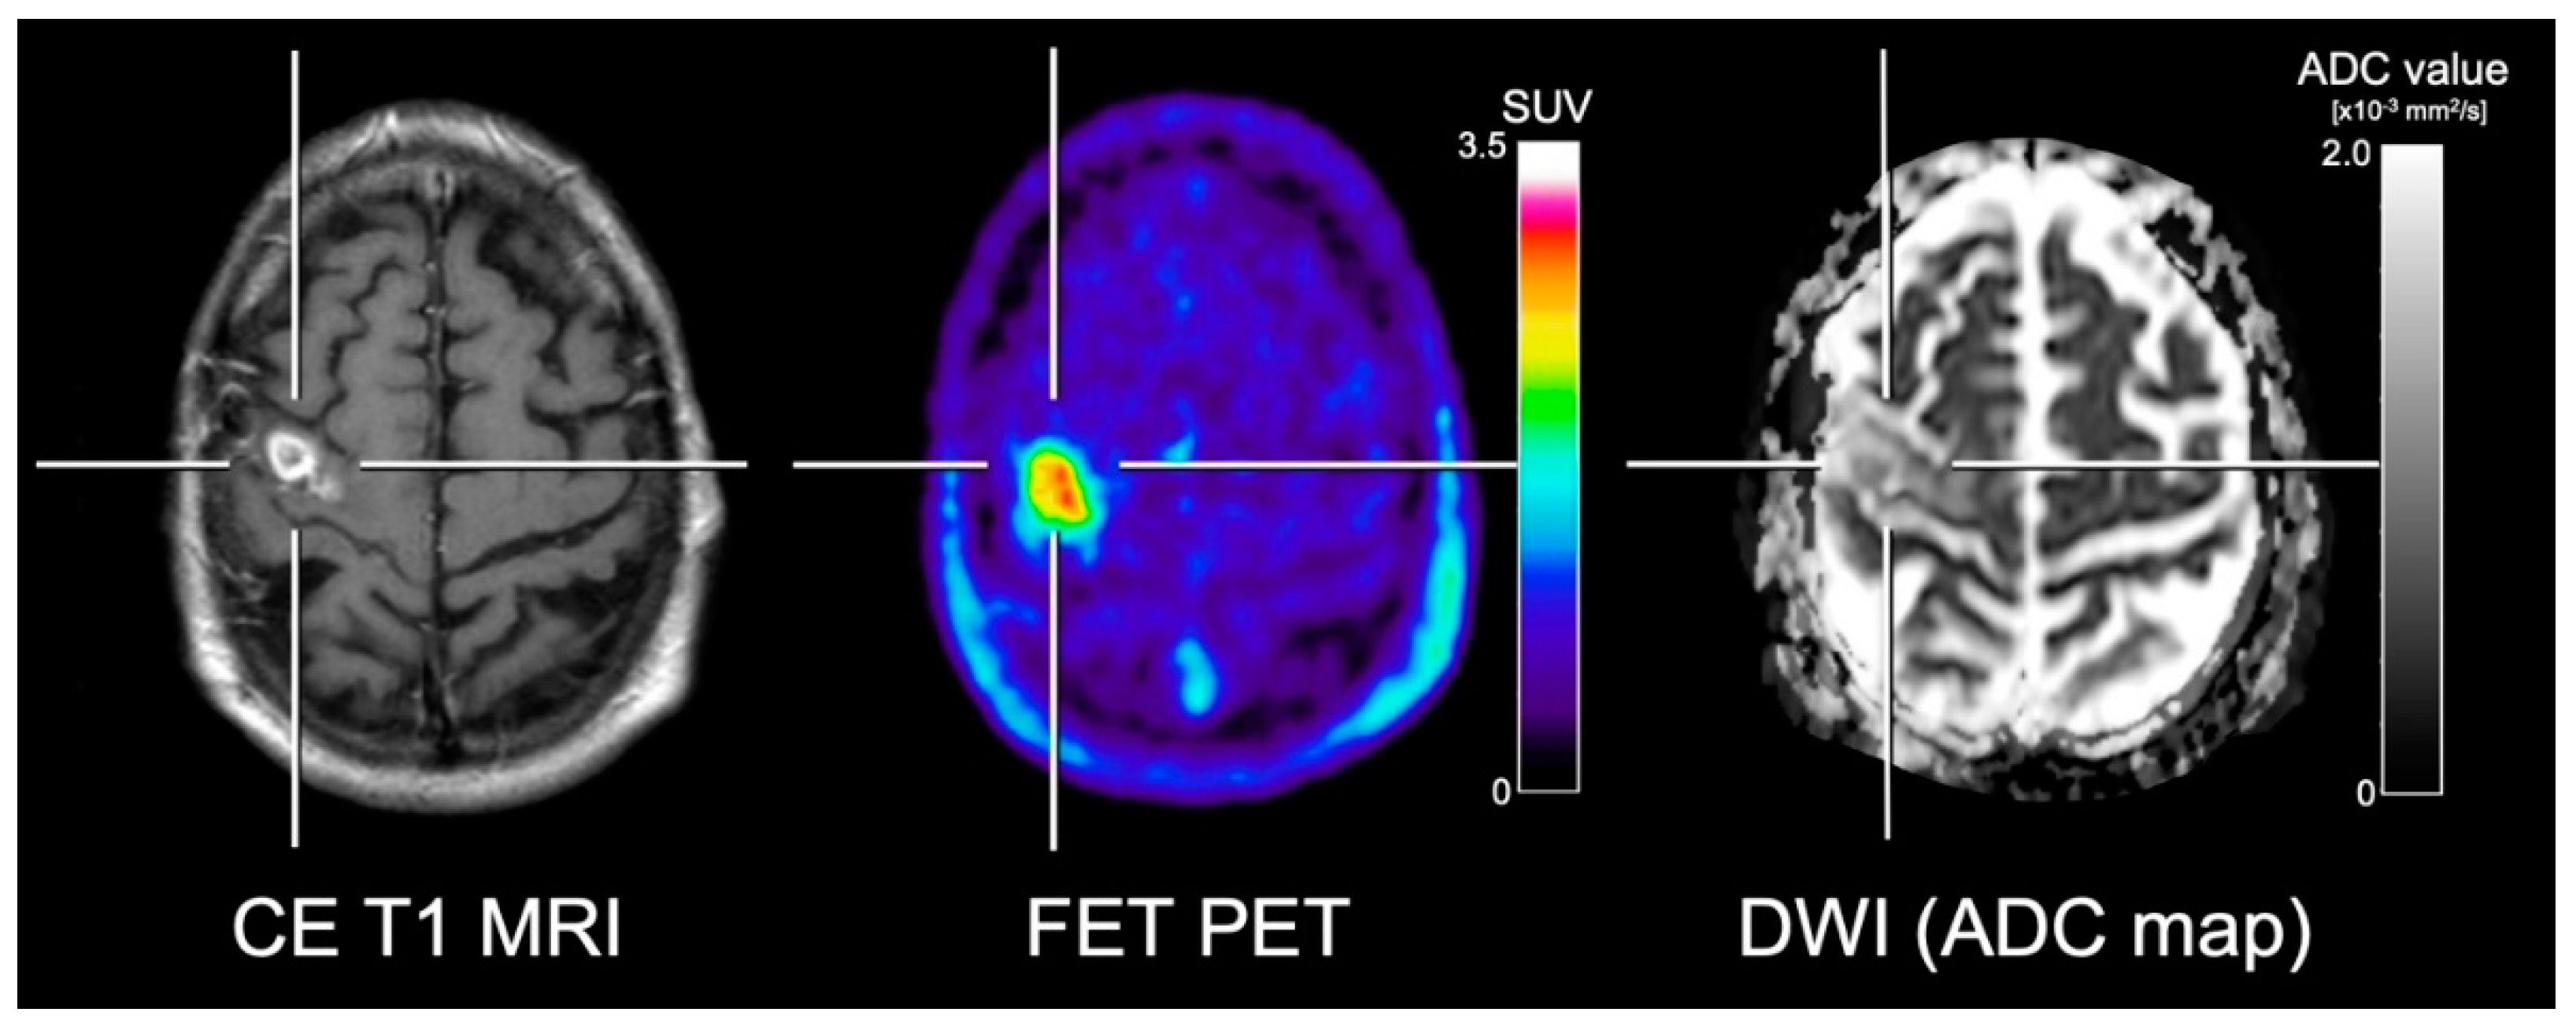

- Karavaeva, E.; Harris, R.J.; Leu, K.; Shabihkhani, M.; Yong, W.H.; Pope, W.B.; Lai, A.; Nghiemphu, P.L.; Liau, L.M.; Chen, W.; et al. Relationship Between [18F]FDOPA PET Uptake, Apparent Diffusion Coefficient (ADC), and Proliferation Rate in Recurrent Malignant Gliomas. Mol. Imaging Biol. 2015, 17, 434–442. [Google Scholar] [CrossRef] [PubMed]

- Rose, S.; Fay, M.; Thomas, P.; Bourgeat, P.; Dowson, N.; Salvado, O.; Gal, Y.; Coulthard, A.; Crozier, S. Correlation of MRI-derived apparent diffusion coefficients in newly diagnosed gliomas with [18F]-fluoro-l-dopa PET: What are we really measuring with minimum ADC? AJNR Am. J. Neuroradiol. 2013, 34, 758–764. [Google Scholar] [CrossRef] [PubMed]

- Choi, H.; Paeng, J.C.; Cheon, G.J.; Park, C.K.; Choi, S.H.; Min, H.S.; Kang, K.W.; Chung, J.K.; Kim, E.E.; Lee, D.S. Correlation of 11C-methionine PET and diffusion-weighted MRI: Is there a complementary diagnostic role for gliomas? Nucl. Med. Commun. 2014, 35, 720–726. [Google Scholar] [CrossRef] [PubMed]

- Popp, I.; Bott, S.; Mix, M.; Oehlke, O.; Schimek-Jasch, T.; Nieder, C.; Nestle, U.; Bock, M.; Yuh, W.T.C.; Meyer, P.T.; et al. Diffusion-weighted MRI and ADC versus FET-PET and GdT1w-MRI for gross tumor volume (GTV) delineation in re-irradiation of recurrent glioblastoma. Radiother. Oncol. 2018. [Google Scholar] [CrossRef]

- Kinoshita, M.; Arita, H.; Okita, Y.; Kagawa, N.; Kishima, H.; Hashimoto, N.; Tanaka, H.; Watanabe, Y.; Shimosegawa, E.; Hatazawa, J.; et al. Comparison of diffusion tensor imaging and (11)C-methionine positron emission tomography for reliable prediction of tumor cell density in gliomas. J. Neurosurg. 2016, 125, 1136–1142. [Google Scholar] [CrossRef]

- Tietze, A.; Boldsen, J.K.; Mouridsen, K.; Ribe, L.; Dyve, S.; Cortnum, S.; Ostergaard, L.; Borghammer, P. Spatial distribution of malignant tissue in gliomas: Correlations of 11C-l-methionine positron emission tomography and perfusion- and diffusion-weighted magnetic resonance imaging. Acta Radiol. 2015, 56, 1135–1144. [Google Scholar] [CrossRef]